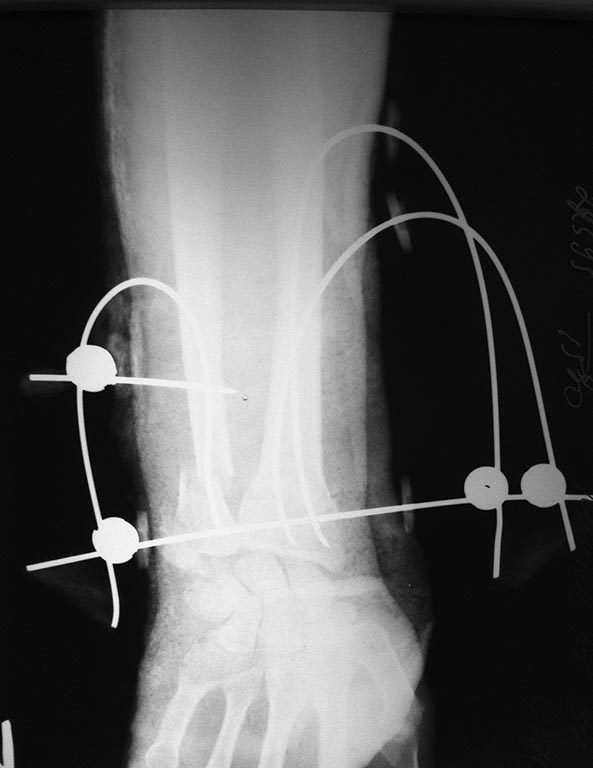

Здравствуйте, уважаемый коллега! К этой спице фиксируются изогнутые спицы, создающие тем самым напряжение. И еще, она проходит трансфрактурно, через внутрисуставной перелом лучевой кости.

А как технически Вы провели изогнутые спицы в лучевую кость? И какое напряжение создается изогнутыми спицами? На снимке этого напряжения не видно.

Ясно. То есть Вы делаете разрез кожи, а потом вбиваете изогнутую спицу. Насколько я понял, то "напряжение" - только умозрительное. И насколько оно "полезно" для обеспечения стабильности-компрессии отломков? Если бы это напряжение было выраженным, то изогнулась бы поперечная спица, а этого на снимке не видно. Может быть я неправильно понимаю какую-то "биомеханику"?

Правильно, я так и понял, что компрессии при таком варианте быть не должно, а должно вроде бы быть "натяжение" дистальной поперечной спицы. Но, извините за излишнюю придирчивость, на рентгенограмме дистальная спица несколько изогнута даже в "обратную" сторону. Из-за чего она так себя ведет, я не понимаю. Ну, с компрессией вроде бы разобрались.

По поводу какого-то влияния "напряжения" в спицах на стабильность перелома я бы тоже говорил с большой осторожностью. Влияние "напряжения" на стабильность кто-то изучал? Если да, то каковы результаты? То есть имеются вопросы по поводу "напряжения" в спицах, поэтому я бы эту тему с "напряжением", на всякий случай, не стал развивать.